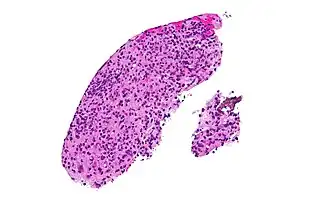

High magnification micrograph of toxoplasmosis -

Brain biopsy-High magnification micrograph of toxoplasmosis -

Immunohistochemistry displaying positive Toxoplasma gondii trophozoites in a brain biopsy of a HIV immunocompromised individual